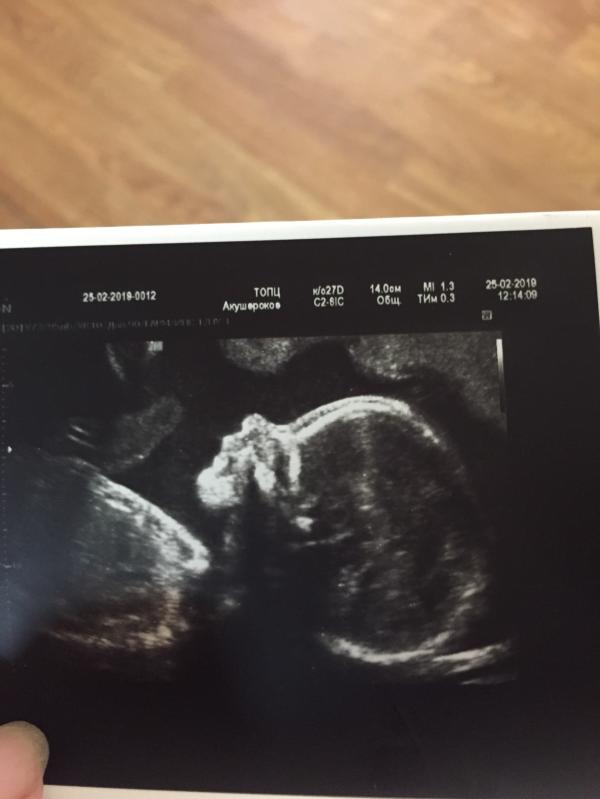

Кисты сосудистых сплетений рассосались!! Ураааа!!

25.02.2019